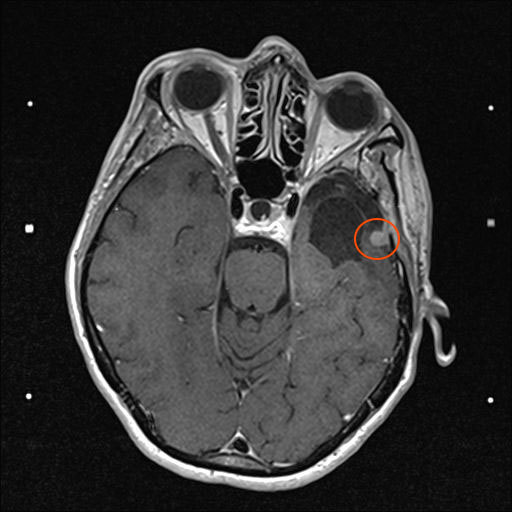

Am 03. November war mein Kontrollbesuch beim MRT. Leider ist ein kleiner Befund aufgetaucht. Schau das Video, dann kannst Du sehen.

Nun kann sich zeigen, ob die menschliche Medizin eine Lösung für mich hat. Möglichkeiten gibt es. Sogar mindestens eine, die der Neurochirurg als fein und elegant beschreibt. Gamma-Knife, eine Strahlentherapie. Klingt etwas nach Star Wars – man wird sehen,  etwas abwarten ist auch drin.

Heute war ich im MRT im Bremen. Der Befund des auswertenden Arztes ist, dass er der Meinung ist, dass der Tumor etwas gewachsen ist. Ich habe mir die Bilder angesehen und versucht diese Aussage zu verstehen. Vermutlich ist sie richtig, aber das Wachstum ist nicht heftig nur vielleicht von 0,7 cm auf 0,8 cm. Aber Gamma-Knife hat es offensichtlich nicht entfernt.

Zu meinem Geburtstag am 27.4. habe ich sehr schöne Geschenke bekommen und kann mich auch über meinen bunten Garten freuen, im Herbst gab es ein Tulpen-Sonderangebot, dem konnte ich nicht wiederstehen! Und nun ist das Ergebnis zu sehen. Am 28. April war wieder mal MRT-Termin. Leider hat es an dem Tag eine Vertretung des auswertenden Arztes gegeben, die Ärztin war super freundlich aber hat keine ganz konkreten Aussagen machen können, aber sie hat mir 2 CDs gebrannt, ich konnte eine gleich bei den Neurochirurgischen Ambulanz abgeben und eine mit nach Hause nehmen. Mein Blick auf die Bilder hat eine nazu unveränderte Lage gezeigt.

Heute war der Termin beim Chirurgen, leider schon um 9:00 Uhr und natürlich wollte ich die knapp 20 km mit dem Rad zurück legen, Stephan wollte gerne mitkommen. Leider war die bereits abgegebenen CD nicht eingelesen worden und so musste erstmal die Datenverarbeitung arbeiten und wir warten, bis wir eine Auskunft bekommen konnten. Fazit: Der bestehende Tumor ist kaum gewachsen. Aber es hat sich leider ein 2. Fund ergeben, sehr klein aber deutlich sichtbar. Aber Maßnahmen sind erstmal nicht notwendig.